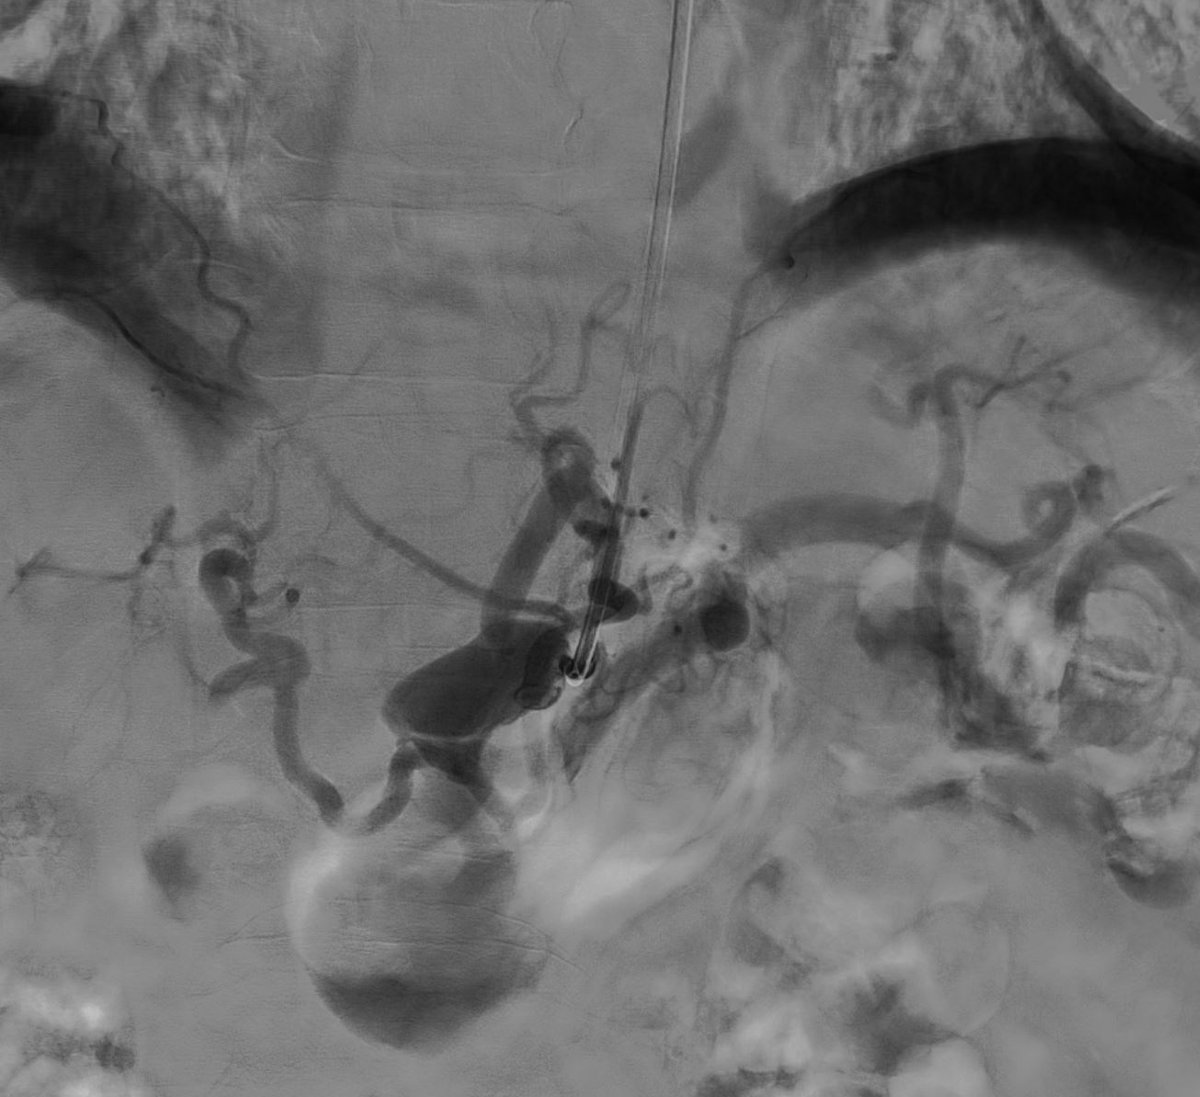

Pancreatic

#AVM with multiple arterial feeders and single outflow into splenic vein branch. Treated via#transportal approach with#coils and a plug. No more AVM. Fun way to start 2020.@MountSinaiIR@GESTSymposium@SIRspecialists@SIRRFS@ISETNewspic.twitter.com/1KRDZIJlPSHvala. Twitter će to iskoristiti za poboljšanje vaše vremenske crte. PoništiPoništi -